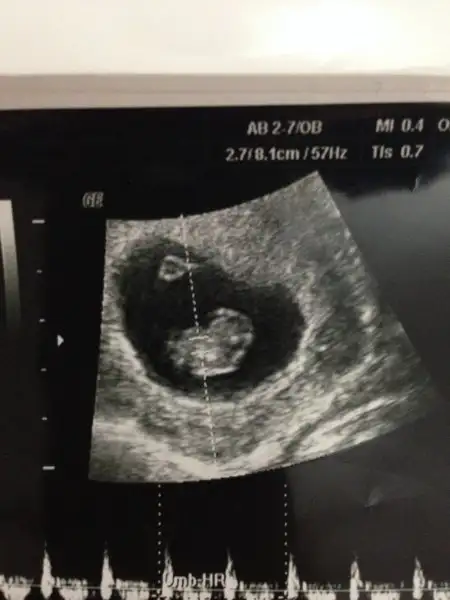

kız gibi canım. Şöyle usg resmini eline aldığında eğer karından usg ise bebek kesenin sağına yakınsa kız soluna yakınsa erkek, vajinal usg ise tam tersi. Buarada sesin ultrason resmi benimkine çok benziyo bebeğin kesedeki konumu olarak

Cnm ben tek sağ sol için yorum yapmıyorum plasentasına falanda bakıyorum hangi yöne yatkınsa hepsi, ona göre söylüyorum

Cnm bu konu başkasınındı o zaman tek sağ sol olarak yorum yapılıyordu ama ben plasenta, kese ve bebek hangi yönde ağırlıktaysa ona göre yorum yapıyorum. Önemli olan ilk USG resmi olsun 6,7,8 haftalık